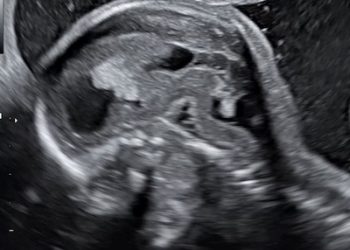

How To Do Febbraio 2024: Istmocele

Cari soci, questo mese un nuovo video "How to do", dedicato allo studio ecografico dell'istmocele Grazie a Daniela Giuliani! Il...